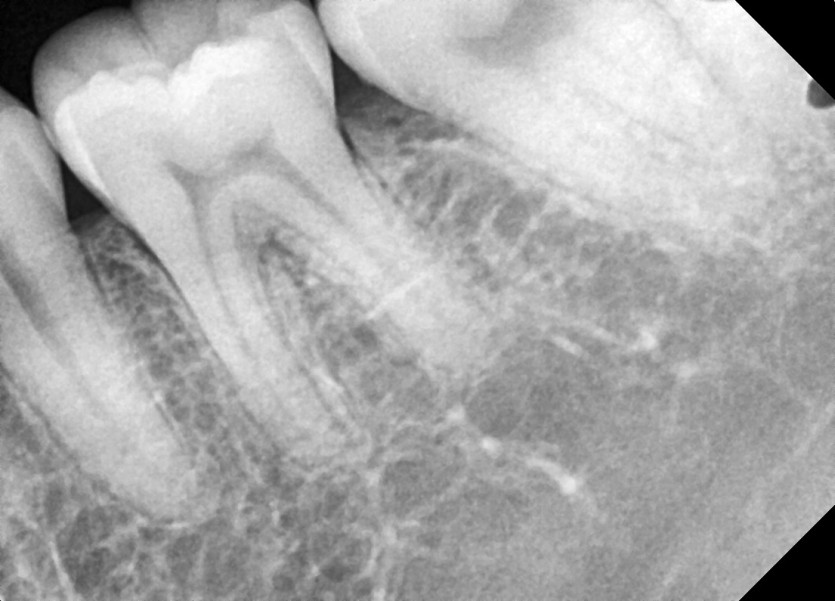

#28, 38 사랑니 발치

구강 외과 전문의가 당일 발치했습니다.